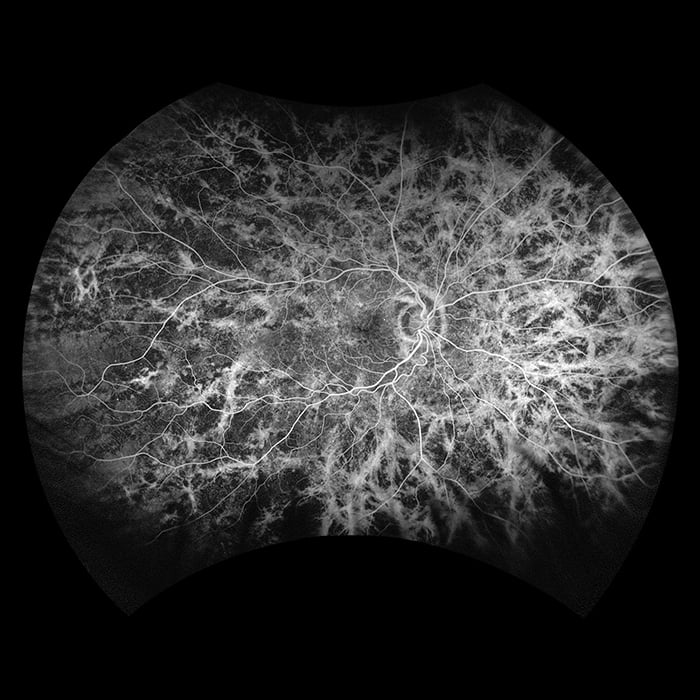

- fa

California was developed for medical imaging and is a standard for retinal screening programs. California is available in multiple models with multiple imaging modality options. California produces a 200°, single shot retinal image of unrivaled clarity in less than ½ second and is changing the management of diseases including Geographic Atrophy, Diabetic Retinopathy, AMD, and Uveitis.